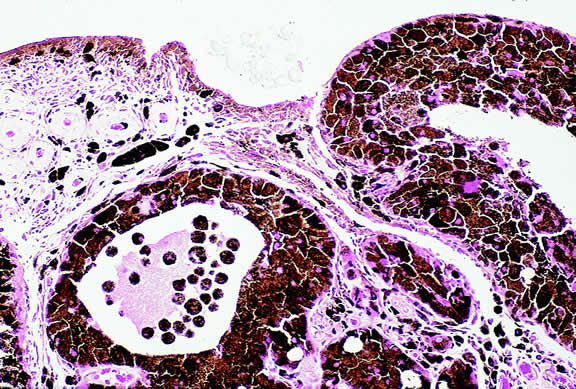

The substrate for the development of melanoma in white patients with ocular melanocytosis is a diffuse nevus that affects all, or part, of the uveal tract. Clinically, the nevus typically is evident as hyperchromic heterochromia iridum, patchy slate gray epibulbar pigmentation, and a darker aspect of the fundus compared with the fellow eye (Fig. 8). A sector of uvea is affected in some patients, however, and the nevus may spare the iris. The uvea in congenital melanocytosis is thickened by an increased number of heavily pigmented nevus cells similar to those found in melanocytomas (Fig. 9). RPE abnormalities such as drusen often develop on the surface of the thickened choroid.48 The sclera also contains patchy foci of pigmentation. The slate gray conjunctival pigment reflects the presence of dendritic melanocytes on the epibulbar tissues deep to the conjunctiva. Nevus of Ota does not predispose to conjunctiva melanoma. However, patients rarely may develop melanomas of the orbit49–51 and even leptomeninges.1,52,53 White patients who have congenital ocular or oculodermal melanocytosis should be followed periodically because of the increased risk of uveal melanoma.54

Fig. 9. Congenital ocular melanocytosis, choroid. Choroidal stroma is thickened by infiltrate of heavily pigmented benign melanocytes. Patient had iris heterochromia and skin pigmentation consistent with nevus of Ota. (Hematoxylin-eosin, × 100.)